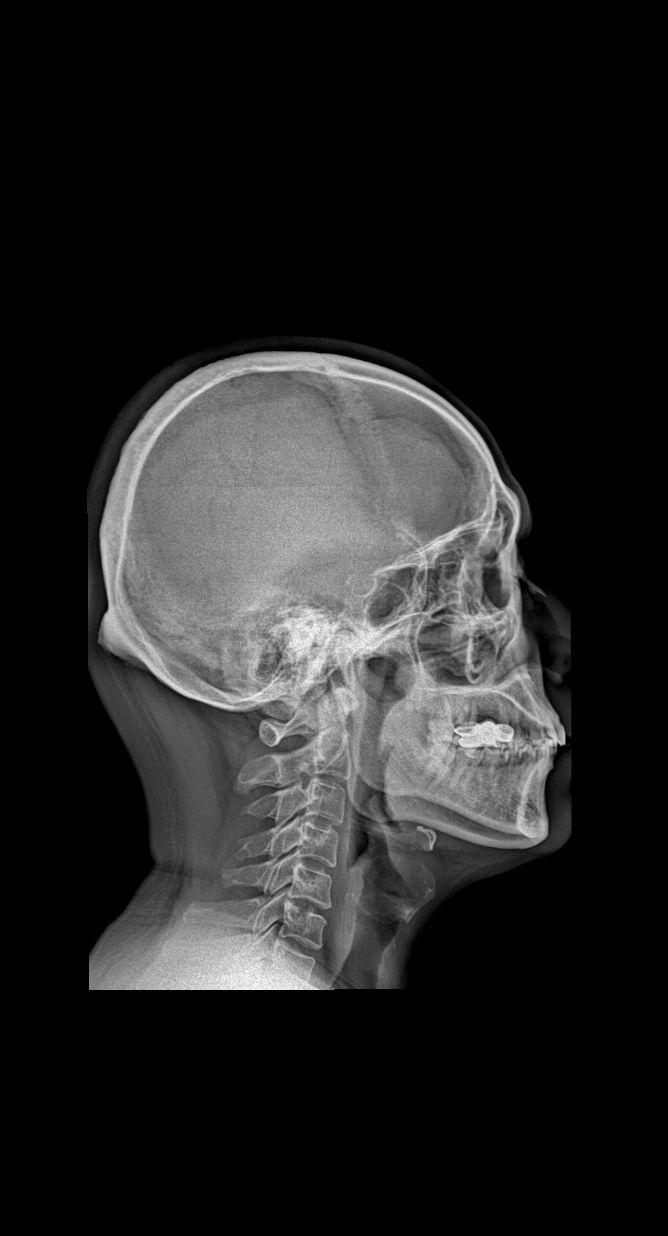

男34 腰椎疼痛 颈椎正侧+腰椎正侧